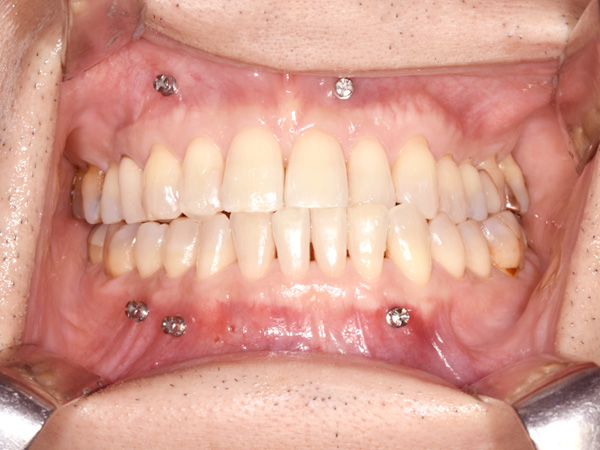

歯の真ん中が上の歯に比べて下の歯は、向かって右にずれています。お口の中の金属は固定用のスクリューです。

右側のかみ合わせを確認しています。

お口の中の状態を確認します。